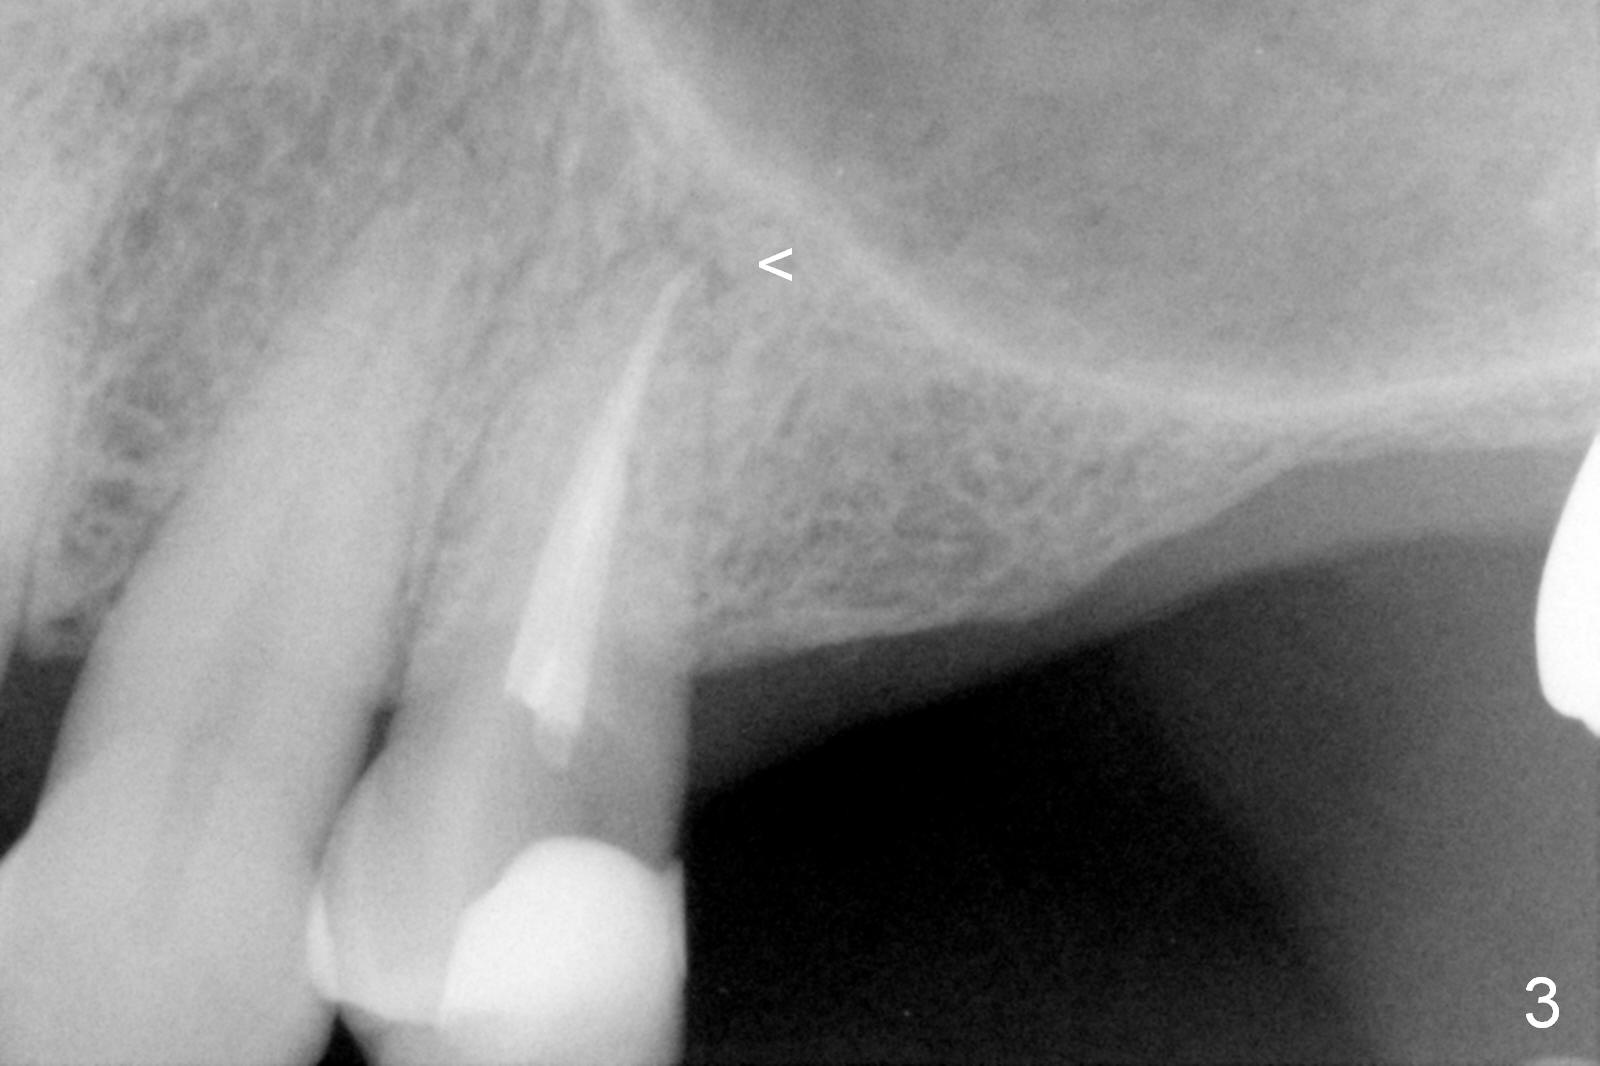

A 64-year-old man (MM) had caries at the tooth #12 (Fig.1), requiring root canal therapy (RCT, Fig.2). One year later, the periapical radiolucency reduces (Fig.3 <, as compared to that in Fig.2). The tooth remains asymptomatic 7 years posts RCT (Fig.4). A year later, the tooth has pain and buccal gingival swelling (probing tenderness); periradicular radiolucency is evident (Fig.5 arrowheads). It appears that the root fractures. Between the 7th and 8th years post RCT, the patient masticated mainly on the left side, while implants were placed at #30 and 31. The patient plans to have 4 implants in the upper left sextant (Fig.6). While implants are being placed at the site of #12 (Clindamycin) and 13, sinus lift seems mandatory at the sites of #13 and (initial depth will be 5-6 mm). By the time implants to be placed at #14 and #15, the bone height may increase.